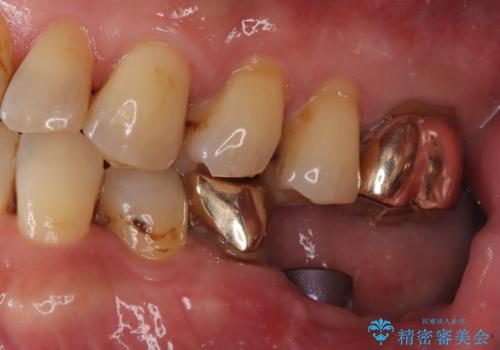

- 「フロスをしたら銀歯が取れた」を主訴に来院された患者様です。虫歯を除去した後、ゴールドインレーで治療を行いました。

隣の歯も虫歯になっており、その歯はCR(保険適応)で治療を行いました。

左上4はゴールドインレー、左上5はCR(保険適応)で治療を行いました。